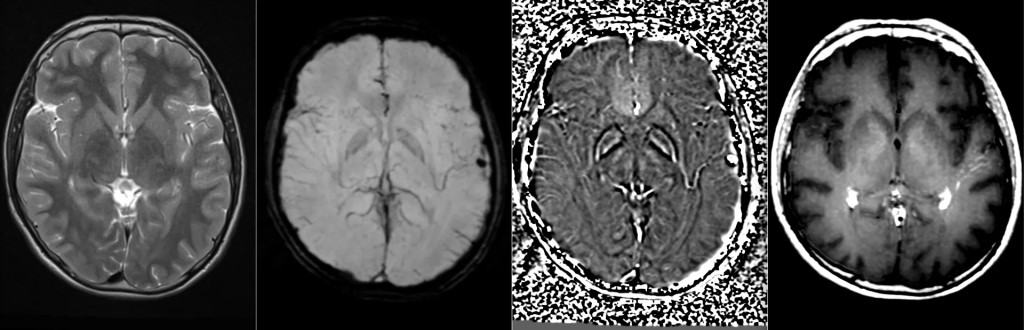

Фото Клинический случай кавернозной мальформации, ассоциированной с венозной аномалией развития (ВАР). Следует напомнить, что ВАР часто сочетаются с каверномами, однако точные статистические данные не привожу, чтобы простимулировать самостоятельный поиск информации и закрепление знаний. Клиническая симптоматика у данного пациента отсутствует, что является типичным сценарием для подобных находок. Диагноз установлен случайно.